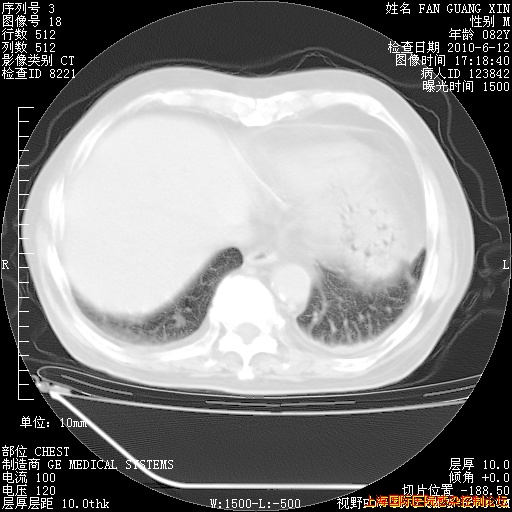

补发6月12日肺部CT肺窗

6月12日肺窗

整整相隔30天的肺部CT好像有所好转啊。甲强龙减量第3天,需要观察体温。